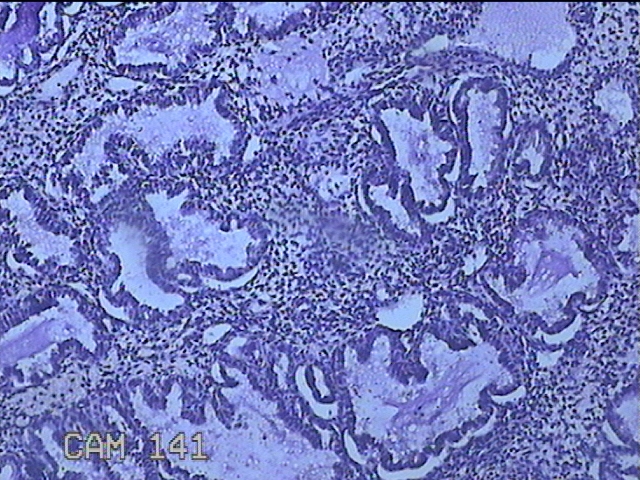

性别

女

年龄

41岁

临床诊断

异常子宫出血;取出子宫内节育器;子宫内膜炎

一般病史

阴道不规则流血2个月。

标本名称

宫腔内容物

大体所见

灰白暗红色不规则碎组织3.5x2.5x0.8cm一堆。